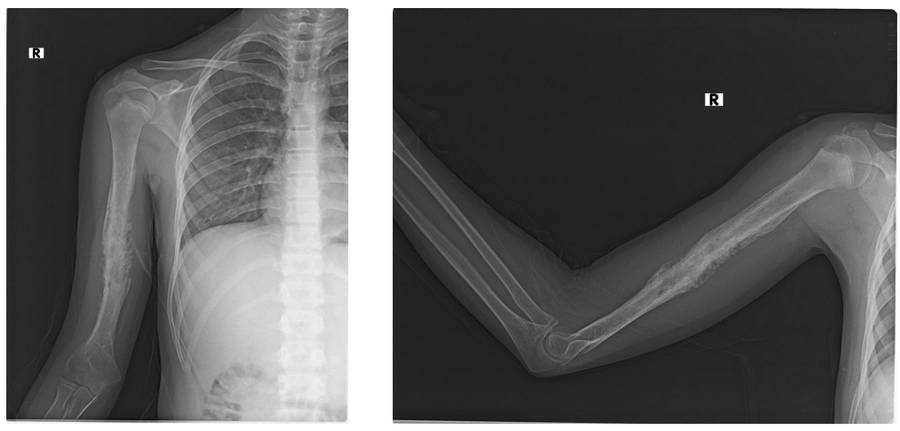

Ameliyat Öncesi: Röntgende humerus diafizde düzensizlik ve harabiyet görülmekte